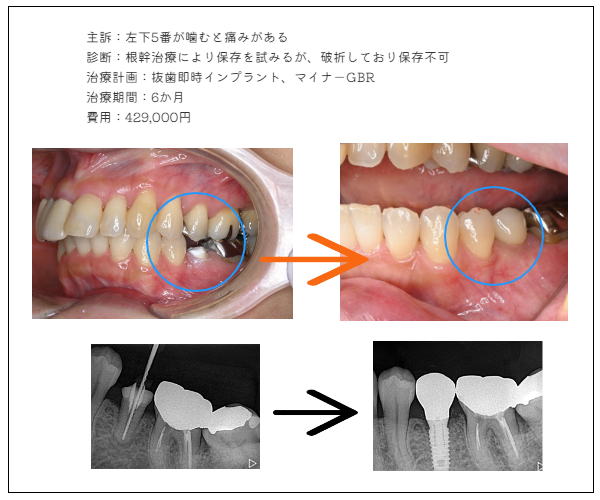

imprant症例2